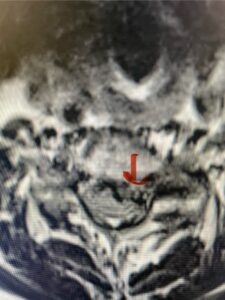

Figures 1a: Sagittal and axial T2-weighted lumbar MRIs demonstrating a grade 1 L2-3 spondylolisthesis (red arrow) with severe stenosis secondary to right L2-3 facet hypertrophy (red arrow).

Fig 1b: Note the left L2-3 facet joint (blue arrow) is normal in size compared to the right (red arrow)